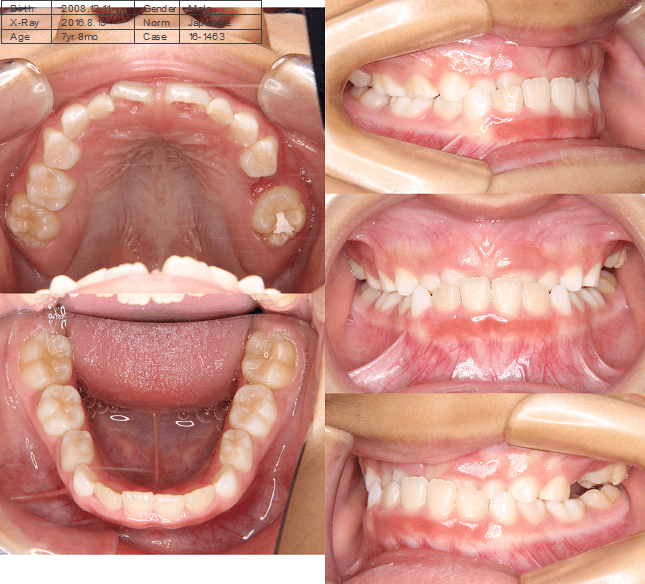

| 年齢・性別 | 7歳8ヶ月の男児 |

|---|---|

| 主訴 | 前歯の噛み合わせが逆で、見た目や食事に違和感があることを心配されて来院されました。 |

| 治療期間・回数 | 3年6ヶ月 |

| 費用 | 430,000円(税別) |